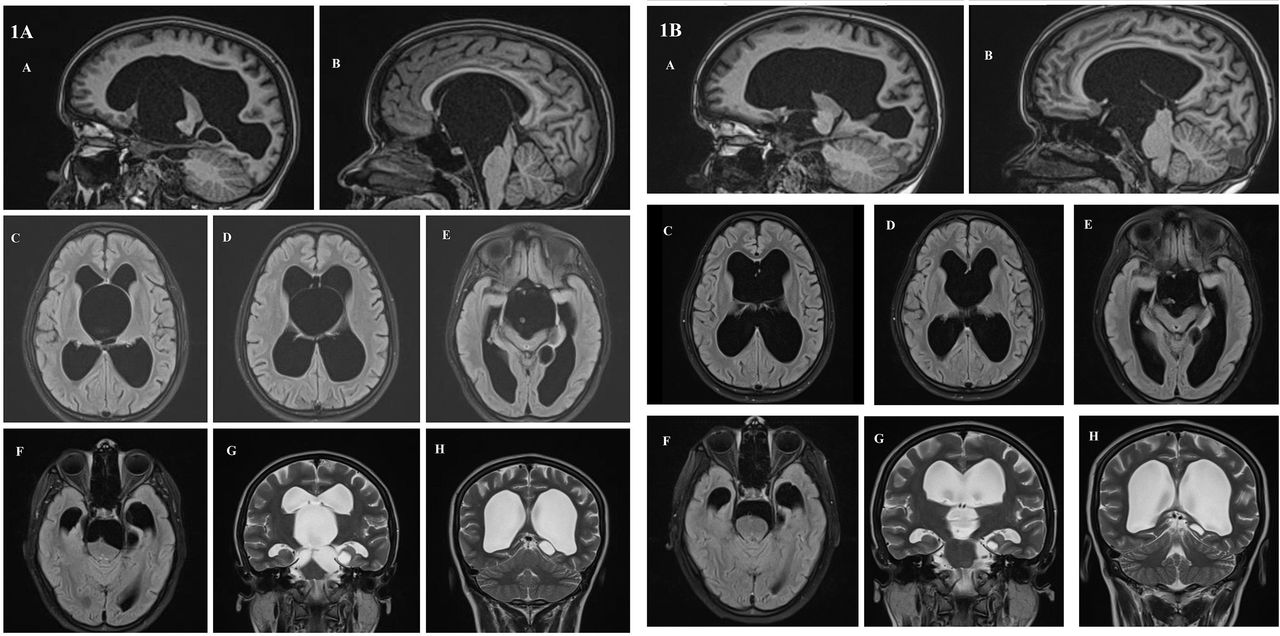

An unusual presentation of bobblehead doll syndrome in a patient with hydranencephaly and

“NoNo” Type BobbleHead Doll Syndrome in an Infant With an Arachnoid Cyst of the Posterior Bobble Head Syndrome The bobble head doll syndrome is a rare neurological disorder characterized by repetitive and involuntary movement of the head that. The signs and symptoms of bhds. The signs and symptoms of bhds. Mri of the head revealed a suprasellar arachnoid cyst and ventriculomegaly. Bobble Head Syndrome.

Bobble‐Head Doll Syndrome in a Child with Suprasellar Arachnoid Cyst Saracoglu 2019 Bobble Head Syndrome Mri of the head revealed a suprasellar arachnoid cyst and ventriculomegaly. The bobble head doll syndrome is a rare neurological disorder characterized by repetitive and involuntary movement of the head that. The signs and symptoms of bhds. The signs and symptoms of bhds. Bobble Head Syndrome.

Bobblehead doll syndrome with suprasellar arachnoid cyst Practical Neurology Bobble Head Syndrome The signs and symptoms of bhds. The bobble head doll syndrome is a rare neurological disorder characterized by repetitive and involuntary movement of the head that. The signs and symptoms of bhds. Mri of the head revealed a suprasellar arachnoid cyst and ventriculomegaly. Bobble Head Syndrome.